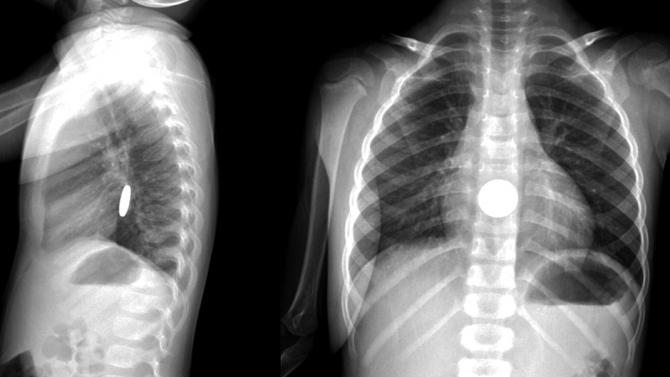

В Луганской области (село Воеводовка Троицкого района) умер маленький ребенок, который проглотил литиевые батарейки. В смерти своей маленькой дочери родители винят медиков, которые не смогли поставить правильный диагноз.

Семья девочки уверяет: ребенок проглотил батарейку неделю назад.

Медики утверждают, что батарейку, девочка проглотила уже после выписки. По факту смерти ребенка прокуратура открыла уголовное производство по статье убийство.